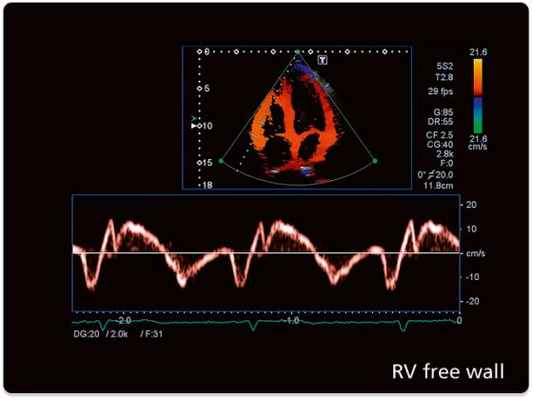

Цветовое допплеровское картирование является разновидностью ИВ допплерографии, при которой кровоток или движение миокарда изображаются разными цветами (обычно красным, синим и зеленым) или их комбинацией, что зависит от скорости, направления и наличия турбулентности.

В каждом участке изображения частотный сдвиг измеряется, преобразуется в цифровой формат, автоматически сопоставляется с заданной цветовой схемой (автокорреляция) и выводится на экран на фоне двухмерного изображения. При оценке кровотока в полостях сердца поток, направленный к датчику и имеющий положительный частотный сдвиг, кодируется оттенками красного. Кровоток, направленный от датчика и имеющий отрицательный частотный сдвиг, колируется оттенками синего.

Оценки в пределах каждого первичного цвета задаются высокими скоростями, не достигающими предела Nyquist. Когда скорость становится выше этого предела, появляется искажение цвета. Турбулентность отражает степень отклонения скоростей в определенной области от средней скорости и кодируется обычно оттенками зеленого.

В связи с этим аномальный кровоток легко распознать по комбинации многочисленных цветов, соответствующих направлениям, скоростям и степени турбулентности. Ширину и размер аномального внутриполостного кровотока используют для оценки степени регургитации на клапанах или выявления впутрисердечных шунтов.

Почти все структурные и гемодинамические сердечные аномалии нарушают кровоток и, следовательно, приводят к изменениям при цветовом допплеровском картировании. Его также используют для определения диастолической дисфункции и длительности фаз сердечного цикла. На рисунке продемонстрированы динамические изменения клапанной регургитации и гемодинамики, записанные с помощью допплерографии и цветового допплера.

Другое важное применение цветового допплеровского картирования — параметрическая визуализация, отражающая характеристики кровотока или скорость движения тканей, включая длительность пиков скорости.

Тканевая допплерография

Тканевая допплерография отражает движение тканей или структур, скорость или частотный сдвиг у которых намного ниже, чем скорость кровотока. При допплерографическом исследовании кровотока измеряют скорость тока эритроцитов (обычно > 20 см/сек, но может достигать 800 см/сек при клапанной патологии). Миокард движется с намного меньшей скоростью (< 30 см/сек), чем кровь, но с более высокой амплитудой отражения. В связи с этим ИВ допплерография была модифицирована для записи низких скоростей движения миокарда и отсечения высоких скоростей кровотока. ТД также может быть представлена в цветовом режиме.

Главное ограничение регистрации скорости движения ткани заключается в том, что при ТД может быть пере- или недооценка реальной скорости или функции тканей из-за поступательного движения или предела ограничений. Анализ скорости деформации (е) миокарда поможет преодолеть эти ограничения путем измерения реальной скорости укорочения и удлинения участка миокарда.

Деформация (с) представляет собой изменение длины во время сокращения и расслабления миокарда, выраженное в %. Укорочение представляют отрицательными, а удлинение — положительными величинами деформации и ее скорости.

Изображение движения тканей (TTI, Tissue Tracking Imaging) — это интеграл скорости движения ткани в течение реального времени. Он помогает оценить локальную сократимость миокарда и улучшить визуальную количественную диагностику нарушений сократительной функции миокарда.